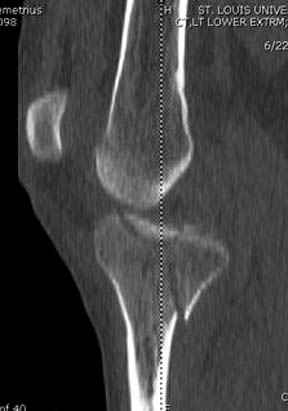

На представленных предоперационных срезах КТ огромный задне-медиальный фрагмент расположен больше кзади, чем медиально. Для планирования, кроме поперечных срезов, надо ориентироваться на корональные срезы, которые укажут топографию верхушки медиального фрагмента.

Здесь как раз тот случай, когда результат зависит не только от мастерства хирурга, но и от наличия современных методов исследования. Например, КТ которая поможет рассчитать направления шурупов и установку импланта. Кроме этого, поможет определиться с доступом.